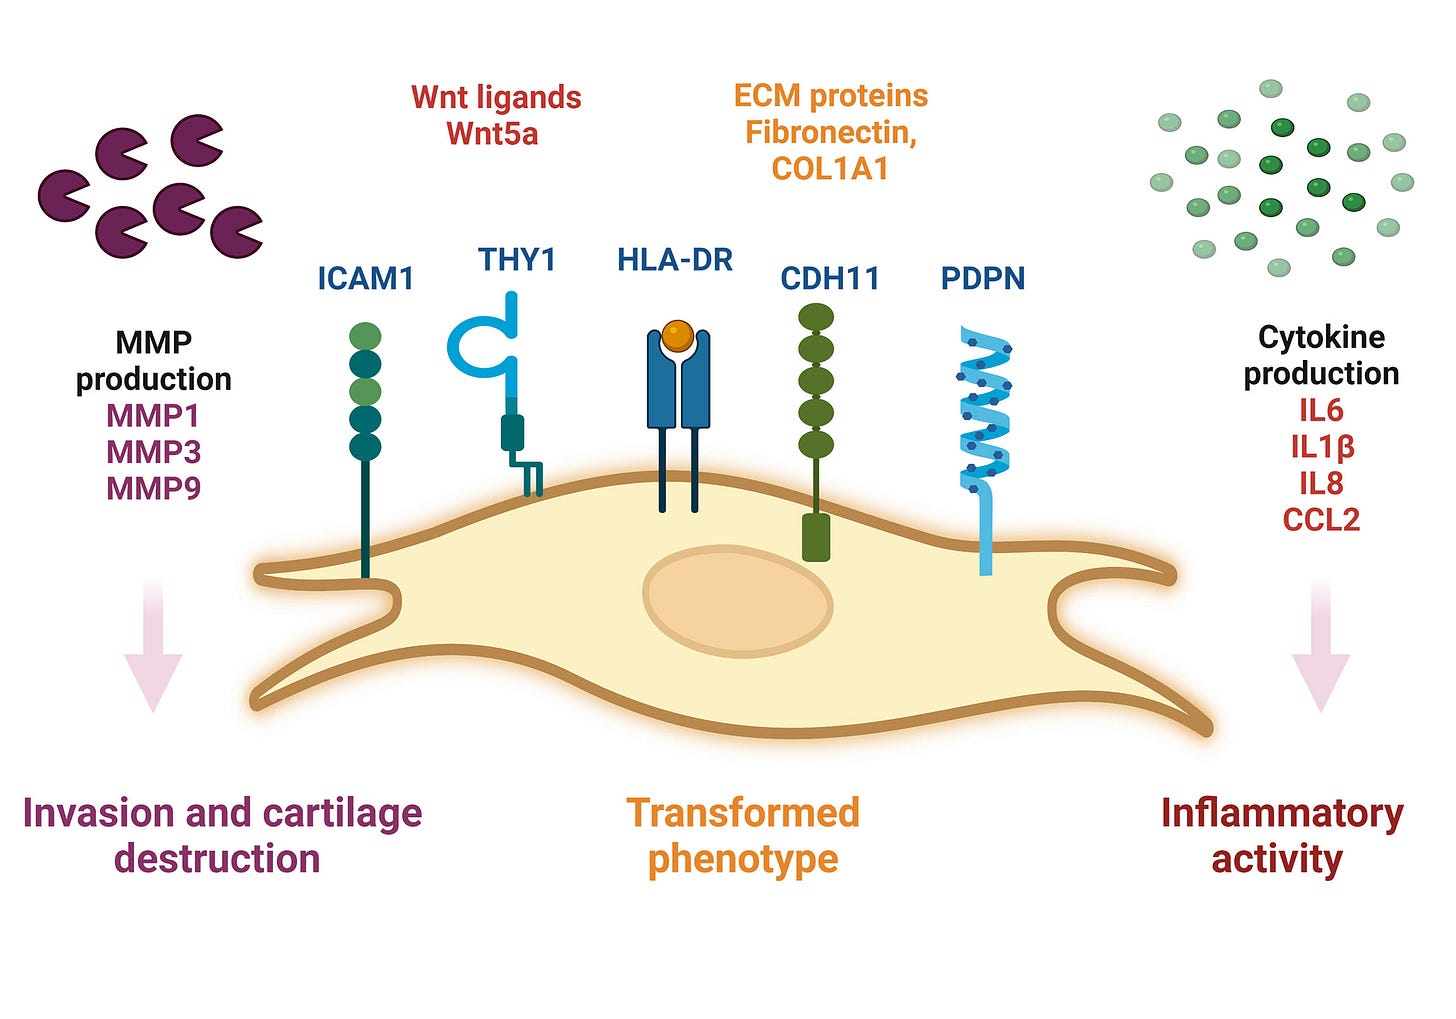

BRD4 and arthritis

Background to fibroblast-like synoviocytes (FLS):

Fibroblast-like synoviocytes (FLS) represent a specialised cell type located inside joints in the synovium. These cells play a crucial role in the pathogenesis of chronic inflammatory diseases, such as rheumatoid arthritis.

…The inner lining of the joint consists of the synovium (also called the synovial membrane), a thin layer located between the joint capsule and the joint cavity. The word "synovium" is derived from the word "synovia" (or synovial fluid), which is a clear, viscous fluid produced by the synovium, and its main purpose is to reduce friction between the joint cartilages during movement. Synovium is also important to maintain proper joint function by providing the structural support and supply of the necessary nutrients to the surrounding cartilage

…FLS that are present in the synovium during RA display altered phenotype compared to the cells present in normal tissues. They lose the property called contact inhibition (cells arrest their growth in the case when more cells come into contact with each other), and they also lose the growth dependency on adhesive surfaces; both these phenomena contribute to the increase in the number of FLS in the inflammatory tissue and are also typical for example for the growth of cancerous cells.

…The aggressive phenotype of FLS in RA and the effect these cells have on their microenvironment can be summarized into hallmarks that distinguish them from healthy FLS. These hallmark features of FLS in RA are divided into 7 cell-intrinsic hallmarks and 4 cell-extrinsic hallmarks. The cell-intrinsic hallmarks are: reduced apoptosis, impaired contact inhibition, increased migratory invasive potential, changed epigenetic landscape, temporal and spatial heterogeneity, genomic instability and mutations, and reprogrammed cellular metabolism. The cell-extrinsic hallmarks of FLS in RA are: promotes osteoclastogenesis and bone erosion, contributes to cartilage degradation, induces synovial angiogenesis, and recruits and stimulates immune cells.

From 2015, Zhang et al used a mouse model to perform an in vivo investigation into the effects of BRD4 inhibition on TNFa-stimulated human rheumatoid arthritis fibroblast-like synoviocytes (RAF-FLS) behaviour21.

RA is about more than just IL-16, IL-17 & Th17 cells, BRD4 is the missing link:

We aimed to explore the effects of bromodomain-containing protein 4 (BRD4) inhibition on tumor necrosis factor (TNF)-α-stimulated human rheumatoid arthritis fibroblast-like synoviocytes (RA-FLS) behavior and the therapeutic implications using BRD4 inhibitor JQ1 were explored in vivo. The levels of interleukin (IL)-1β, IL-6, IL-17 and IL-18 in cultural supernatants from TNFα-stimulated RA-FLS were measured by ELISA. RA-FLS migration and invasion in vitro were investigated using wound healing and Matrigel assay. Expression of signaling pathway proteins was measured by Western blot. The in vivo effects of BRD4 inhibitor JQ1 were elucidated using collagen-induced arthritis (CIA) mice. We found BRD4 silencing reduced the secretion of IL-1β, IL-6, IL-17 and IL-18 from TNFα-stimulated human RA-FLS. Downregulation of BRD4 inhibited FBS-induced migration and invasion of human RA-FLS. BRD4 silencing decreased the phosphorylation of c-Jun and activation of NFκB in TNFα-stimulated RA-FLS. In vivo, BRD4 inhibitor JQ1 reduced the inflammatory response, autoantibody production and joint damage of CIA model. Our data suggest for the first time that BRD4 inhibition has anti-inflammatory property in RA.